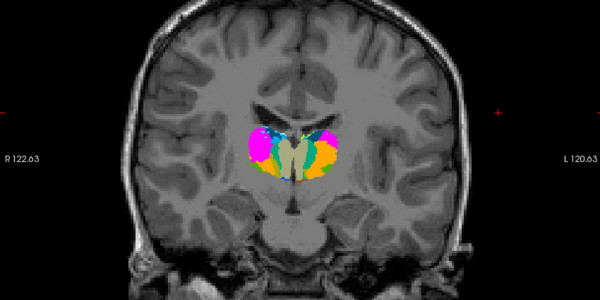

Irakurtzen ikasteko prozesua argitzeko ikerketa bat abiatu du BCBL zentroak

BCBL Basque Center on Cognition, Brain and Language ikerketa zentroak abian du Dysthal proiektua, D ereduko haur eta nerabeen irakurketa estrategiak ikertzeko eta irakurketa prozesuan parte hartzen duten mekanismo neurobiologikoak ikusteko. Gipuzkoako 9-16 urte bitarteko mila haur eta neraberekin egingo dute ikerketa.